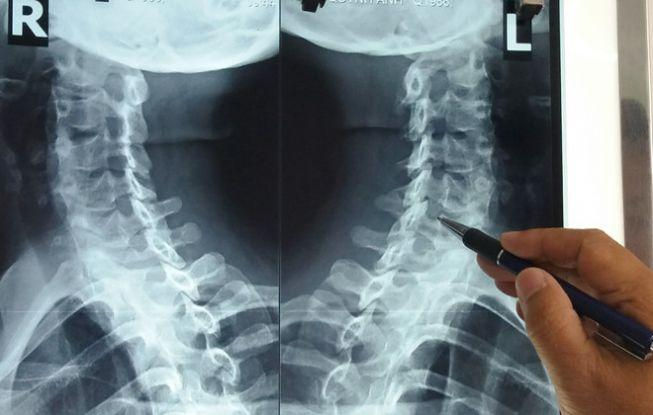

Mỏi cổ gáy, vai và đau nửa đầu, hạn chế vận động mỗi khi xoay trở khớp cổ là những triệu chứng của thoái hóa đốt sống cổ - bệnh đang âm thầm tấn công giới văn phòng.

Bác sĩ Đỗ Tân Khoa, Trưởng khoa Khám bệnh, Bệnh viện Y học cổ truyền TP.HCM, cho biết khoảng 50%bệnh nhân bị thoái hóa đốt sống cổ thường làm nghề kế toán, ngân hàng, văn phòng. Thy là một trong các bệnh nhân rất trẻ mắc căn bệnh này.

Bác sĩ Khoa cho biết thêm bệnh lý này nặng hơn bởi thần kinh bị chèn ép, khiến bệnh nhâncó biểu hiện đau, tê lan xuống bả vai và cánh tay. Dây thần kinh chèn xuống nhánh xương hoành tạo nên những cơn đau thắt ngực khiến nhiều người lầm tưởng là đau tim. Căn bệnh sẽ gây rối loạn giấc ngủ, khi thức giấc rất nặng nề, đôi khi hay quên những việc vừa xảy ra, kém tập trung và đau nửa đầu.

Nguyên nhân dẫn tới thoái hóađốt sống cổ một phần là lãohóatự nhiên cơ thể. Song, đa số bệnh nhân đến khám thường do thói quen sinh hoạt tác động lên sụn khớp. Điển hình là tư thế ngồi máy tính không đúng cách, ngủ ngồi, ngửa cổ trên ghế, gập, ngửa cổ nhiều.